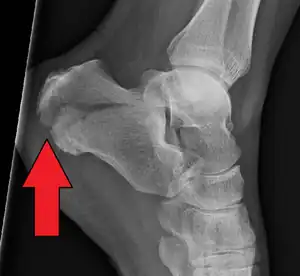

The Angle of Gissane, or "Critical Angle", is the angle formed by the downward and upward slopes of the calcaneal superior surface. On a lateral radiograph, an angle of Gissane > 130° suggests fracture of the posterior subtalar joint surface. Bohler's angle, or the "Tuber Angle", is another normal anatomic landmark seen in lateral radiographs. It is formed by the intersection of 1) a line from the highest point of the posterior articular facet to the highest point of the posterior tuberosity, and 2) a line from the former to the highest point on the anterior articular facet. Bohler's angle is normally 25° to 40°.[13] A decreased angle is indicative of a calcaneal fracture.